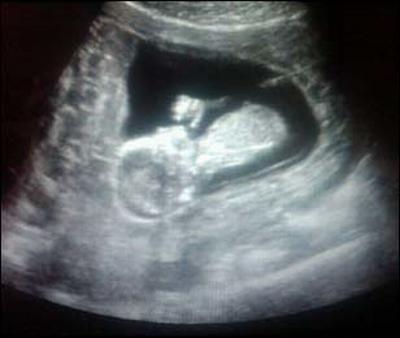

A cantora Fey, que recentemente confirmou sua gravidez e seu próximo casamento com seu noivo Alonso Orozco, publicou imagens da ultrasonografia do seu primeiro filho.

A cantora publicou a imagem através de sua conta no Twitter.

Fey publica ultrasonografia de seu primeiro filho